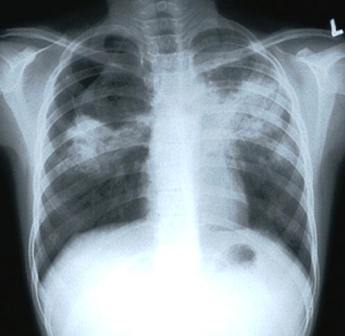

Causes Symptoms And Precautions Of Tuberculosis Formally Called T.b